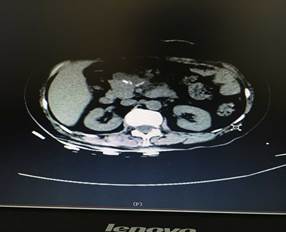

近日,我院肝膽外科入住一位65歲老年女性患者。該患者是一位退休工人,平日生活樸素,一年前自覺有上腹部隱痛不適,每次腹痛發(fā)作便自行于藥店買藥“治療”??墒墙螘r間,該患者感覺腹痛進行性加重,腹部出現(xiàn)隆起,進食少量食物便會出現(xiàn)腹脹、惡心、嘔吐不適,遂來我院就診。門診行腹部CT檢查發(fā)現(xiàn)胰腺巨大占位性病變(圖1),此時患者才恍然大悟,立即入住肝膽外科進行治療。

圖1